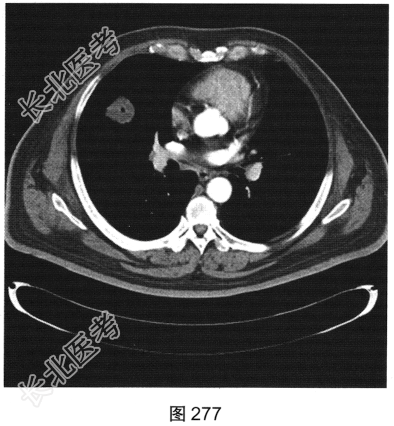

- [材料题] 患者男性,56岁,因“查体发现右肺中叶结节半个月余”就诊。患者于半个月前在小汤山疗养院查体时行胸部X线检查,显示右肺中叶结节,遂至我院就诊。行胸部CT检查:显示右肺中叶外侧段有一肿块影,大小为3.6cm×3.2cm,可见分叶,边缘有毛刺,内见空泡影,CT值约15HU,增强后CT值约25HU。患者近期无咳嗽、咳痰,无咯血、胸痛,无发热、乏力,无声音嘶哑、饮水呛咳,无头痛、头晕,未予特殊治疗。为进一步诊治,以“右肺占位”收入我院。患者精神状态良好,体力、食欲、睡眠正常,体重无明显变化,大、小便正常。胸部CT检查如图274~图277所示。

- 多项选择题2.根据患者临床病史和影像特征,您的诊断是( )

A、周围型肺癌

B、真菌球

C、结核球

D、寄生虫

E、良性肿瘤

F、机化性肺炎